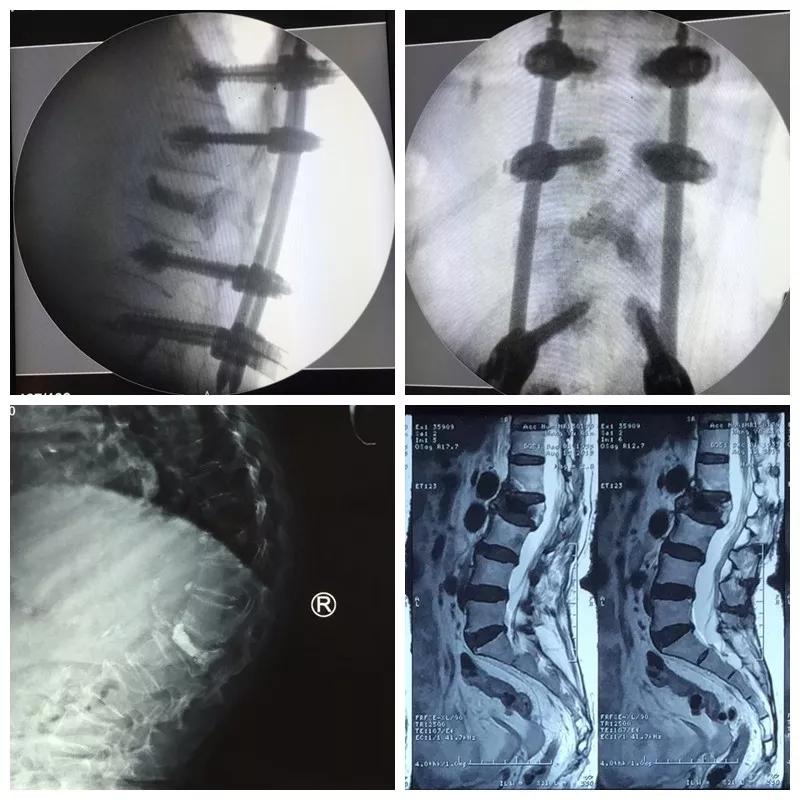

近日,六合彩生肖 骨一科微创团队为一位85岁高龄的患者,运用骨水泥钉道强化技术治疗腰椎骨折后再发后凸畸形,效果满意。

王奶奶今年85岁,1年前摔倒后因骨质疏松导致了腰2椎体压缩骨折,行介入骨水泥治疗,疼痛解除,效果满意。可是后来王奶奶不小心再一次摔倒,驼背明显加重,并又出现了顽固的腰背疼痛和右下肢抽麻,家人把王奶奶送到医院,检查后发现,因为严重的骨质疏松,虽然之前骨水泥加强了骨折椎体,但是没有能阻止骨质疏松的加重,再次摔倒又发生了新的骨折,并且骨折块压住了神经,引起下肢抽麻疼痛。骨一科微创团队经过严谨的术前讨计划与准备,给王奶奶实施了微创手术,一次麻醉同时完成了骨水泥钉道强化矫形、神经减压、新发骨折椎体成形术等三个微创手术,术后驼背畸形纠正、下肢抽麻缓解、腰背骨折疼痛解除,效果理想。老人术后驼背改善了、腰背挺直了,再也不用弯着腰低着头走路了,身高也增加了七八公分,老人开心的说道“我觉得自己又年轻了十几岁”。

郭华院长介绍:骨水泥治疗骨质疏松性压缩骨折已成为常规有效的手术,但是对于严重骨质疏松的患者,单纯骨水泥不能够阻止脊柱后凸畸形的发生,传统椎弓根钉棒系统治疗脊柱骨折矫形效果好,但在严重疏松的骨质里没有足够的把持力,而我们采用的骨水泥强化钉道技术把两者优点结合起来,克服了骨质疏松钉子无把持力的技术难题,而且再加入经皮微创置钉技术,可以完美解决老人的后凸畸形问题。